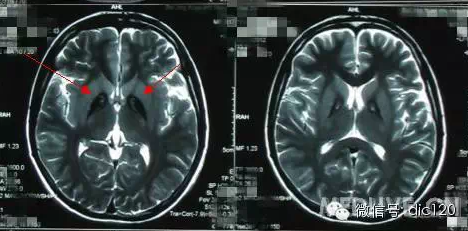

診斷小腦萎縮通常需要進(jìn)行神經(jīng)系統(tǒng)檢查、影像學(xué)檢查(如腦部CT或MRI)和實(shí)驗(yàn)室測(cè)試,治療小腦萎縮的方法主要包括藥物治療、物理治療和康復(fù)訓(xùn)練等,藥物治療旨在緩解癥狀和改善生活質(zhì)量,物理治療幫助患者恢復(fù)肌肉力量和運(yùn)動(dòng)功能,康復(fù)訓(xùn)練則包括語言治療、認(rèn)知訓(xùn)練和心理支持等。